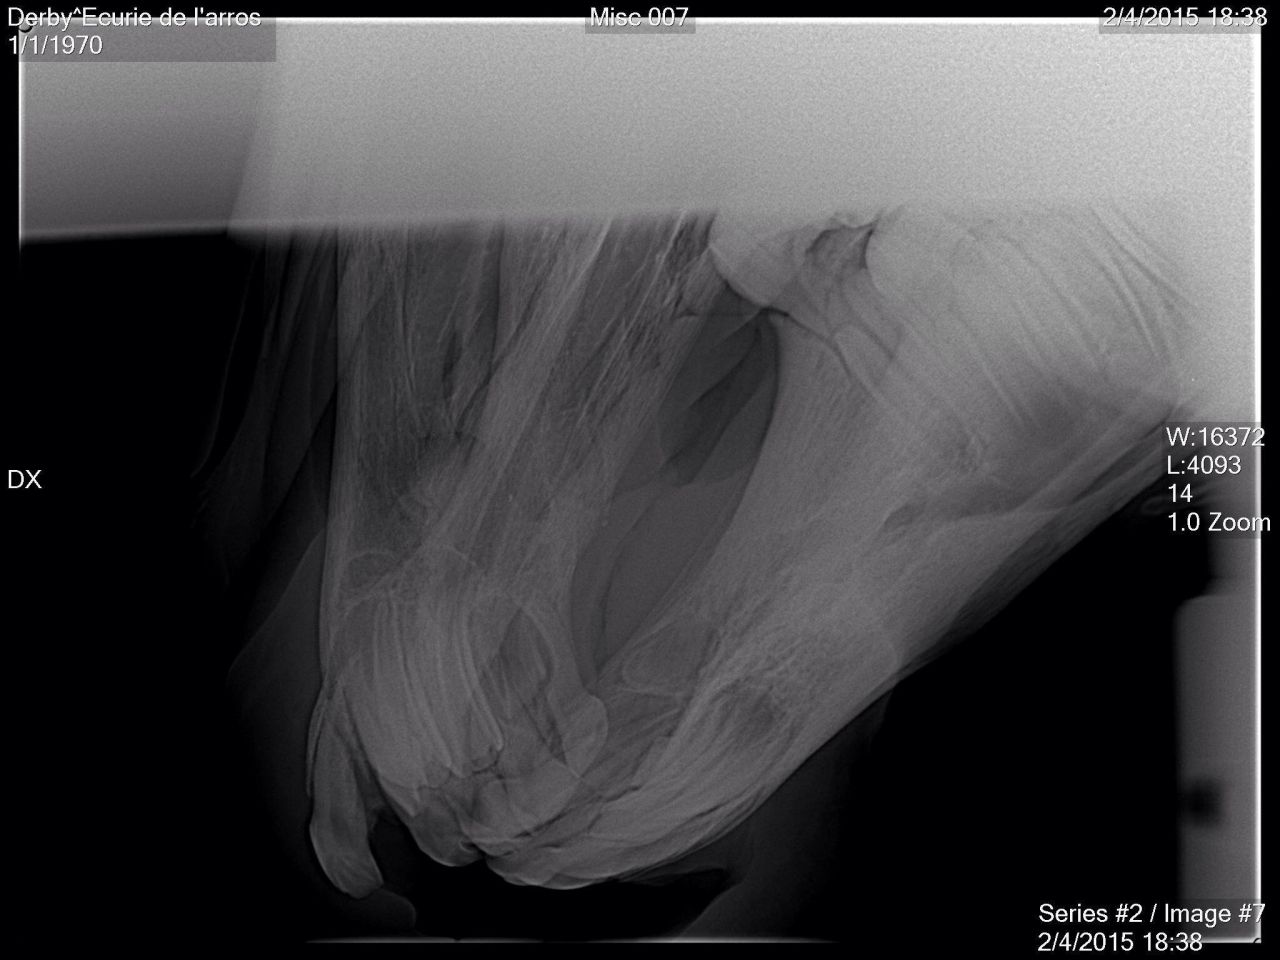

| Dire merci | Bonjour à tous, j ai un poulain de 2 ans qui a vu la dentiste il y a un mois très exactement parce qu il avait les molaires trop longues ce qui lui avait provoqué des coupures. La dentiste est venue a limé l’excédent, tout est rentré dans l'ordre le poney a commencé à reprendre du poids. Ce matin en faisant son box je trouvais qu il avait une odeur étrange, je lui ai ouvert la bouche et voici ce que j ai trouvé... Je ne comprends pas comment un tel décalage a pu avoir lieu en l espace d un mois seulement (évidemment les dents étaient parfaitement alignées au premier passage de la dentiste il n avait aucun soucis). Le poney est au box, depuis un mois, je n'ai pas vu de sang dans le box qui serait signe d'un éventuel arrachement, il va super bien, beaucoup mieux depuis le passage de la dentiste qui l'a vraiment soulagé. J'ai évidemment contacté ma dentiste et ma véto, elles viennent vendredi pour tenter de prendre des radios voir s'il ne s'agit que de muqueuses ou d'os également... Zondez pour mon petit loup, qu'il n'est rien d'irrémédiable. Et si vous avez également eu ce type d’expériences je suis preneuse de tout conseil... Merci pour lui ![]() ![]() ![]() |

| Dire merci | Finalement on sera fixé demain après midi, la véto passe pour les radios, son associée pense à une fracture.... |

| Dire merci | Tout d abord desolee de ne pas vous avoir donné des nouvelles plus tôt . Le loulou va parfaitement bien, la dent etait bien fracturée, un cerclage a été réalise par l ecole veto de Nantes. Il est resté en place 6 semaines avant d être enlevé. Aujourdhui il est de nouveau au pré avec ses copains et tout va pour le mieux pour lui. Voici quelques photos: ![]() [/url] |

| Dire merci | Et une fois le cerclage réalisé, l intervention a duré 2 bonnes heures, le chirurgien a beaucoup gratté la gencive pour pouvoir remettre la dent à sa place. Le travail realisé est vraiment superbe, on ne se rend aujourdhui quasiment plus compte de ce qui lui est arrivé.![]() [/url] |

| Dire merci | Wahou c'était impressionnant Super si tout est rentré dans l'ordre !Spoiler

Pis faut voir le côté positif, t'as une superbe radio de ton mousqueton maintenant